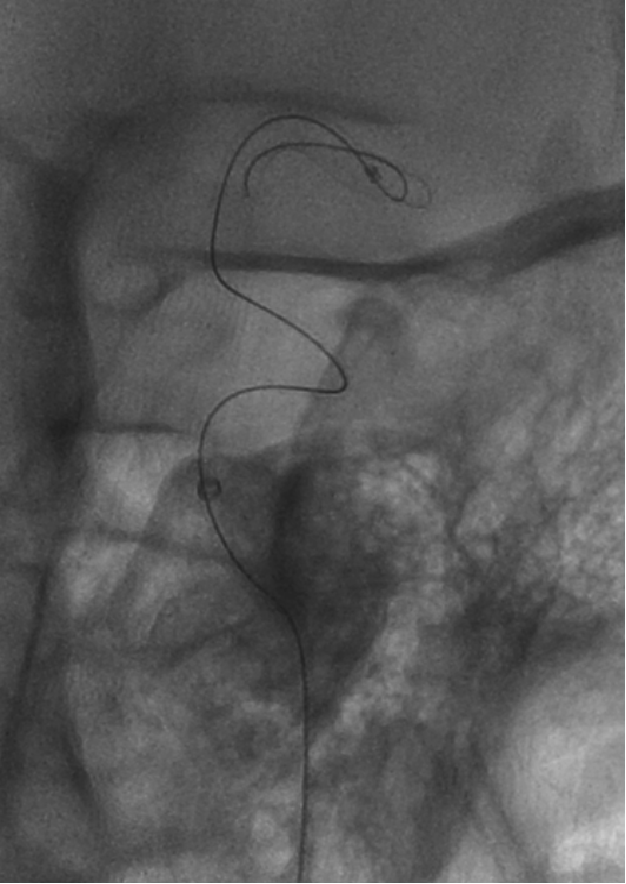

术前造影

造影显示:左侧A1段血流纤细,左侧前循环供血通过右侧A1段及前交通代偿。

左侧颈内动脉末端梭形夹层动脉瘤,2.9mm*3.5mm。